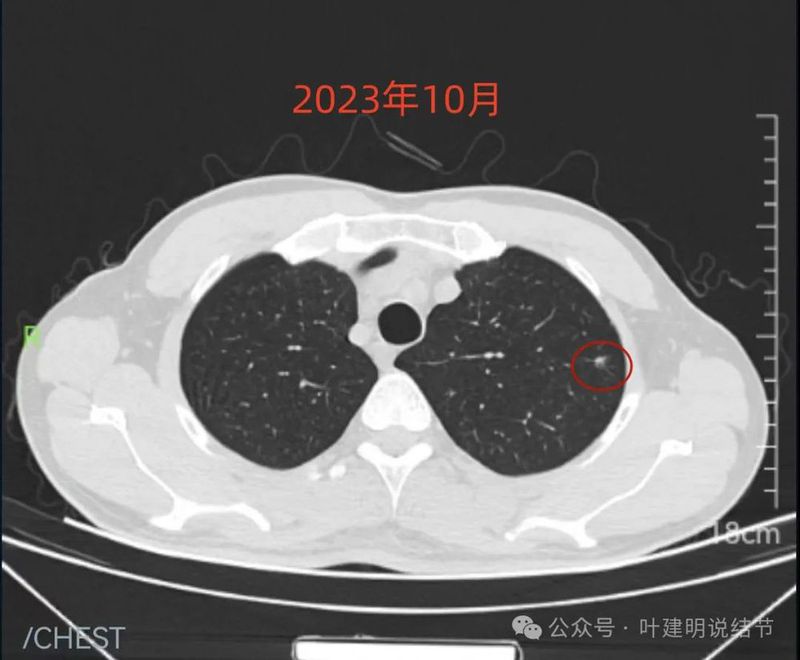

先看不同时间的明显层面截图:

2023年10月时右侧病灶没有明显进展。

2023年10月时左侧病灶较前略明显,便仍觉得密度从高到低有移行,由于整体轮廓较前明显,恶性的可能性增加了。

红色的就是报告上所主要的病灶,右肺中叶的,这个病灶是磨玻璃结节,整体轮廓清楚,瘤肺边界也清,是要考虑是肿瘤范畴的。但是它密度低,没有实性成分,目前风险还不大,还没有到一定要干预的程度,或许在观察三年5年8年也不见得一定会进展。我的想法是再观察一下,半年到一年之间复查都可以。蓝色的界限欠清,实性部分密度过高,像炎性点。意见供参考!